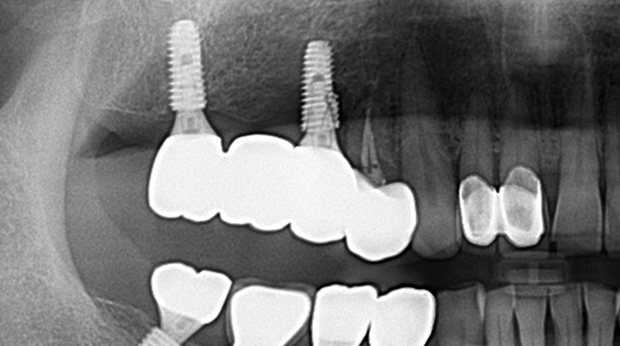

의식하진정법(수면마취)/임플란트

고난도 수술 진료

임플란트와 사랑니 발치는 외과적 시술로 잇몸을 절개하는 외과적 시술은

짧으면 짧을 수록 시술 후 붓기와 통증이 최소화됩니다.

치과의사 경력 14년차 구강외과 전문의가 빠르고 안전하게, 아프지 않게 수술해 드립니다.